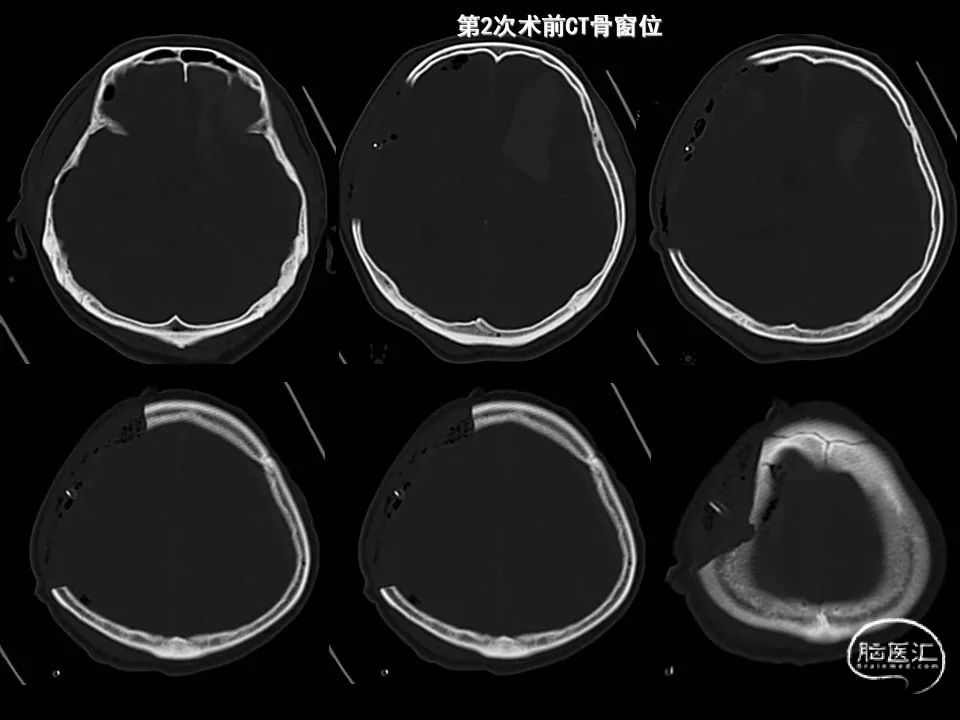

今天为大家分享的是《监测有道丨颅脑创伤-神经重症周刊》第338期,由海南省人民医院朱蔚林教授带来的:2例脑出血微创手术,欢迎阅读、分享。